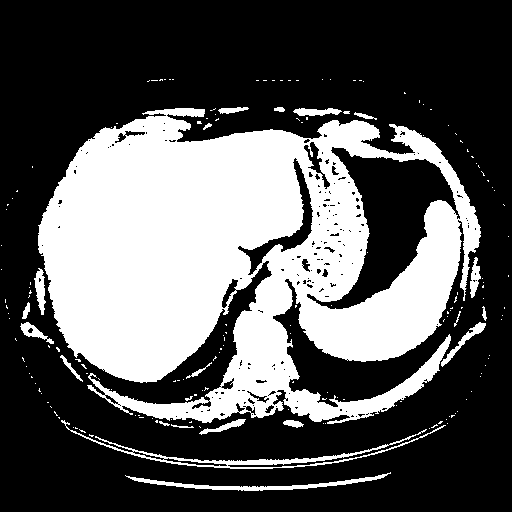

Original NATIVE CT scan (input)

Full window (WL 1023.5, WW 4095 β†’ Low βˆ’1024, High +3071)

Actual HU range: [-1024.0, 3071.0]